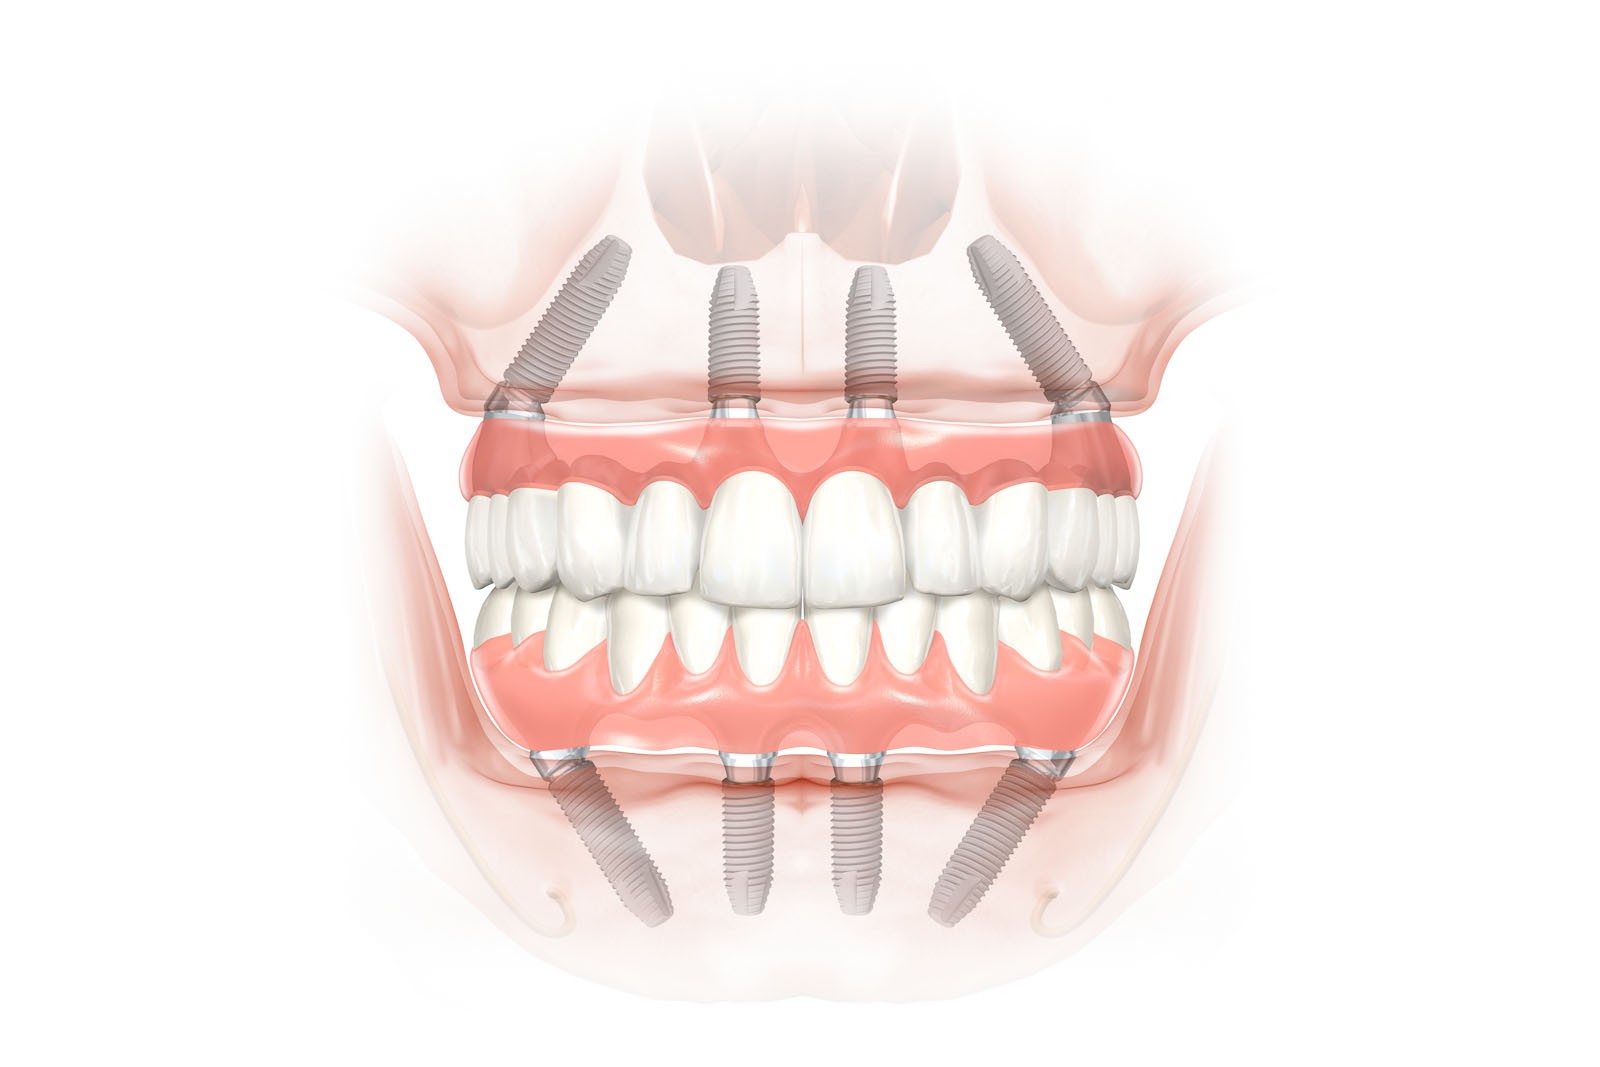

- Implantacja równolegle i symetrycznie wszczepionych implantów z maksymalnym wykorzystaniem podłoża kostnego żuchwy. Proponowana ilość implantów to 4, 6, 8, 10 oraz każda inna w zależności od stanu kości oraz projektu uzupełnienia protetycznego. Implantacje często łączone są z procedurami regeneracyjnymi dla kości, które stanowią warunek prawidłowego wgajania wszczepów stomatologicznych.

Nie ma takiej konieczności. Z biologicznego punktu widzenia jest to nawet niewskazane. Regułą i standardem w odbudowie protetycznej uzębienia jest rekonstrukcja górnego, jak i dolnego łuku zębowego od pierwszego trzonowca po stronie prawej do pierwszego zęba trzonowego po stronie lewej. W oparciu o diagnostykę obrazową (OPG, CBCT) standardowo oceniamy jakość i objętość kości oraz planujemy leczenie, bazując na prognozowanej ilości wszczepianych implantów. W zależności od zaplanowanych rozwiązań protetycznych ich ilość zwykle waha się od dwóch do dziesięciu implantów jako fundament dla rekonstrukcji uzębienia górnego lub dolnego łuku zębowego.

– 6 do 10 implantów – dla stałych uzupełnień protetycznych – mostów

Przy bezzębiu zawsze istnieje możliwość wykonania uzupełnień protetycznych bez zastosowania implantów i są to całkowite protezy osiadające. W zależności od stanu kości szczęk i żuchwy można wykonać protezy lub mosty mocowane na implantach. Mocowanie protez na implantach może być rozłączne, jak w przypadku protez Overdenture, zwanych również nakładowymi. Oznacza to, że proteza w każdej chwili może być odczepiona od platform implantów przez pacjenta i wyjęta z jamy ustnej. Najbardziej jednak pożądane przez pacjentów rozwiązania protetyczne przy bezzębiu to stabilne, niezdejmowalne mosty, które cementuje się lub przykręca na stałe do implantów. One najlepiej imitują estetykę i funkcję naturalnego uzębienia.

Protezy całkowite, zwane osiadającymi, ze względu na to, że leżą równomiernie na podłożu protetycznym, tj. całym podniebieniu oraz części zębodołowej kości szczęk lub żuchwy, czyli tam, gdzie kiedyś były zęby. Utrzymują się stabilnie dzięki dobremu dopasowaniu do podłoża, choć z drugiej strony dobrze dopasowana proteza osiadająca równomiernie uciska poprzez dziąsło całą kość podstawy szczęk. Powoduje to zaburzenia w mikrokrążeniu krwi, co w konsekwencji doprowadza do zaniku kości. Protezy i mosty wsparte na implantach przenoszą siły powstające w procesie żucia przez osie implantów wszczepionych w kość, co najbardziej zbliża ten układ działania do fizjologicznych warunków z uzębieniem, który jest optymalny dla zdrowia i zachowania tkanek. W ten sposób przenoszona siła, o ile ilość implantów jest dobrana właściwie, powoduje wzmocnienie kości, nie zaś jej resorpcję, czyli zanik.